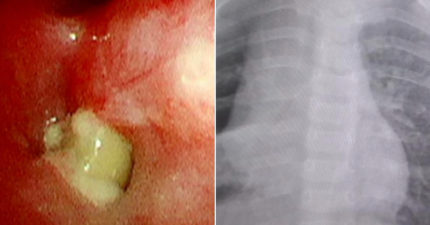

她貼痠痛貼布「引發胃潰瘍」 醫一聽用法震驚